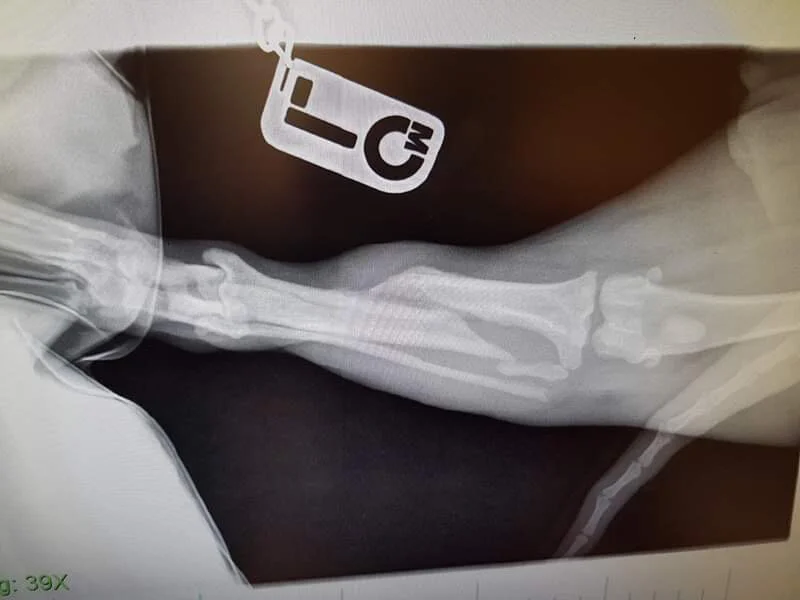

SAFE Perth works to save Suki's broken leg

Suki (pronounced Sookie) came into the care of SAFE Perth after flying from Broome on 16/12/19. Suki has a spiral fracture in her back left leg that is estimated to be 1-3 months old.

Due to the complexity of the fracture and the age of the injury, we are not yet sure which treatment path will work. We have started by trying to save the leg, at a cost of $2500. If this fails, Suki will need her leg amputated which will increase her vet bill even more.